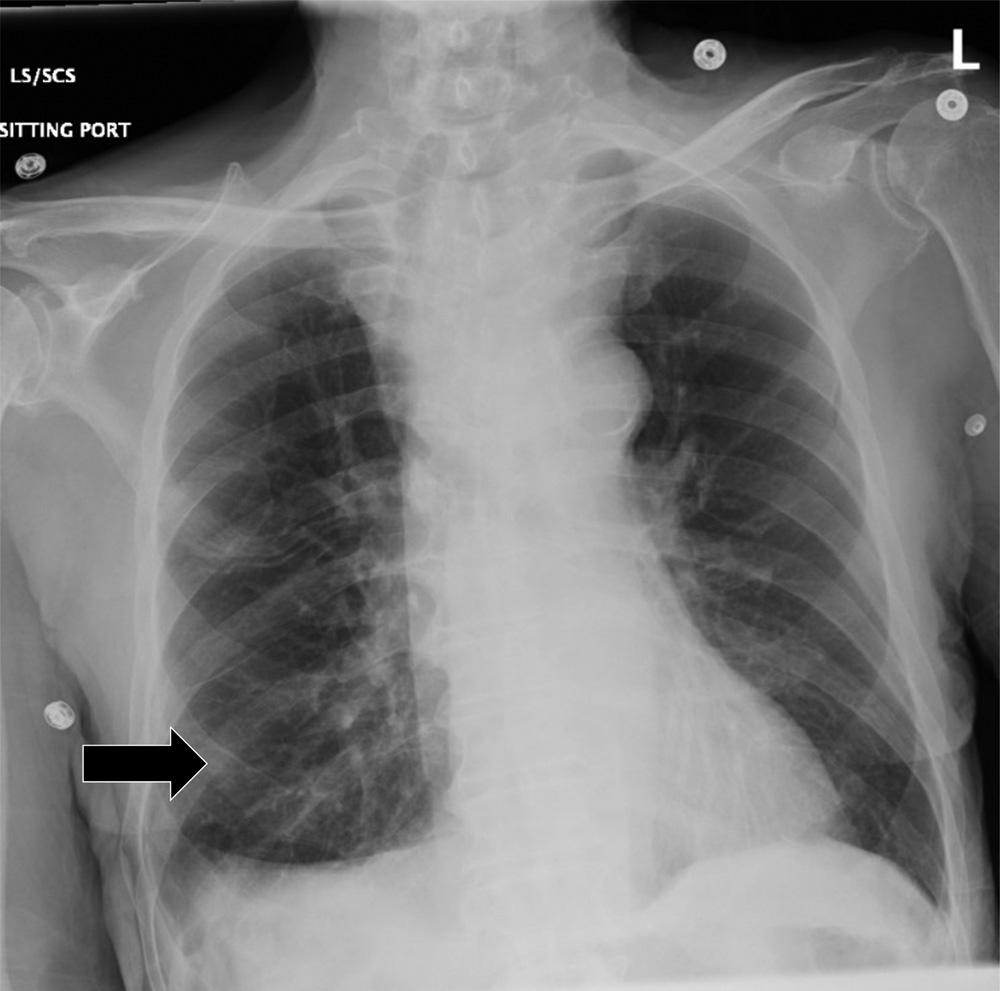

Initiallaboratoryresultsareshownin Table.An electrocardiogram(ECG)wasperformedandshowedasinus rhythmwithoutectopyorST-segmentchangesandwas unchangedfromhisprevioushospitalization.Chest radiography(CXR)wasobtained,shownin Image1.The radiologist’sinterpretationwas “[p]atchyopacityintheright lowerlobesuggestiveofpneumoniainthecorrectclinical setting.Goiterredemonstratedwhencomparedtoprevious. Normalcardiac findings.” Apoint-of-careultrasound (POCUS)oftheheartshowednopericardialeffusion,no suggestionofrightventriclestrain,novolumeoverload,and anormalleftventricle.

Image1. Initialchestradiographshowinganopacityintheright midlung(blackarrow)ina77-year-oldmanbeforeheexperienced arapidchangeinmentalstatus.

Lookingoverthelabsandimaging,Idonotbelievethey provideasignificantamountofnewinformationbutcouldbe usedtoremovesomedifferentials.Thepatient’schemistry hadsomeslightabnormalitiesbutnothingunexpectedgiven hiscomorbidities.Hiscoagulationstudieswereconsistent withsomeonewithcirrhosis.Thereweresomeabnormalities inhisthyroidfunctionpanel,butIdonotthinktheyexplain hisacutechange.Wealsodonotknowthetimingofhis levothyroxinedose,andhisthyroidstimulatinghormone indicatesthathehaslikelybeentakingit.Theetiologyof hematuriaisunclear,buthisurineisotherwisewithoutany signofinfection.Hiscompletebloodcountdoesshow leukocytosisaswellasmildanemia.Lastly,hisCXRis subtle,butanopacityintherightmidlung,asinterpretedby radiology,wouldbeconsistentwithhisabnormal breathsounds.